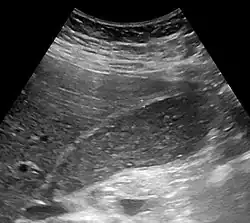

Abdominal ultrasonography showing biliary sludge and gallstones

Gallbladder hepatization, which is biliary sludge filling the entire gallbladder, giving it an echogenicity similar to the liver (seen at left). The patient had a stone in the cystic duct.